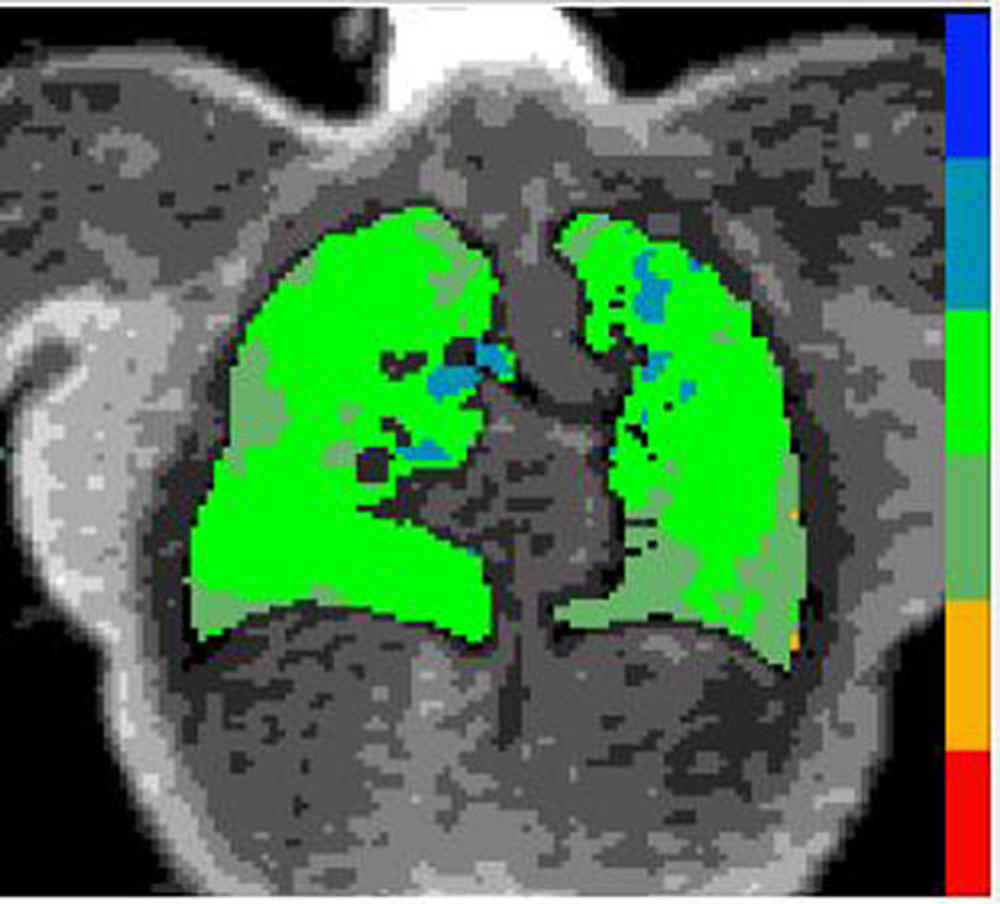

Figure 4. Gas exchange map - Medium

High-res (TIF) version

Figure 2. Individuals in the study are plotted with x-axis being rank of pulmonary gas exchange. The black dots show the pulmonary gas exchange ratio, which in this case is the red blood cell to tissue plasma ratio (RBC:mem), on the left y-axis and the blue dots are the cognition scores on the right y-axis. Gas exchange maps of three representative patients from a low, medium and high pulmonary gas exchange.